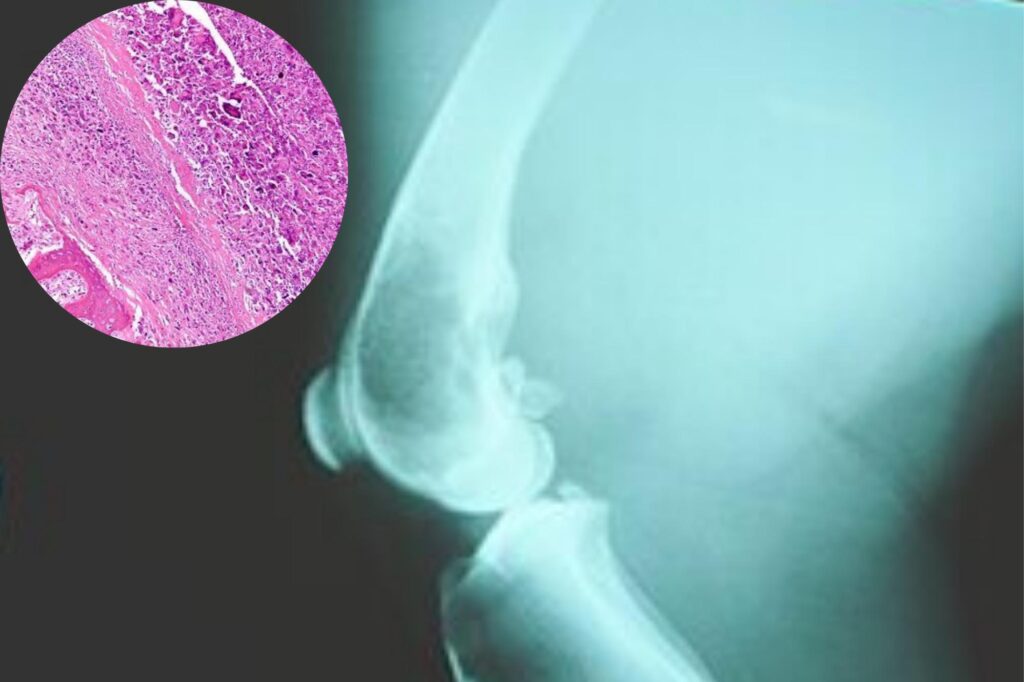

To confirm the suspicion of disease, paleontologists teamed up with radiologists and oncologists, the same specialists who diagnose cancer in people today. They used state-of-the-art CT scans and microscopic analysis, comparing the ancient bone with modern samples of cancerous tissue. This advanced, collaborative approach allowed scientists to look beyond the surface and trace the internal, tell-tale growth patterns of disease, transforming the fossil from a historical artifact into a verifiable medical record.

The form of cancer found was identified as osteosarcoma, a fast-growing cancer that creates irregular, disorganized bone tissue. Remarkably, the internal architecture of the diseased dinosaur bone closely matches the patterns seen in human patients with the same type of cancer today. This striking consistency, separated by millions of years and vast evolutionary differences, suggests that the fundamental cellular mechanisms that govern growth, and their potential to malfunction, are deeply conserved across the evolutionary history of vertebrates.